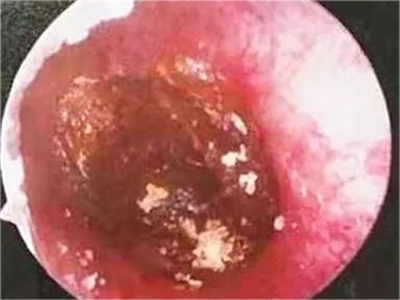

外耳道耵聍栓塞耳内有黑褐色团块图

外耳道耵聍栓塞患者的外耳道内有一个黑褐色硬块,表面凹凸不平,边缘有黄色鳞屑覆盖,并不断堆积在黑色硬块上,使硬块逐渐增大。